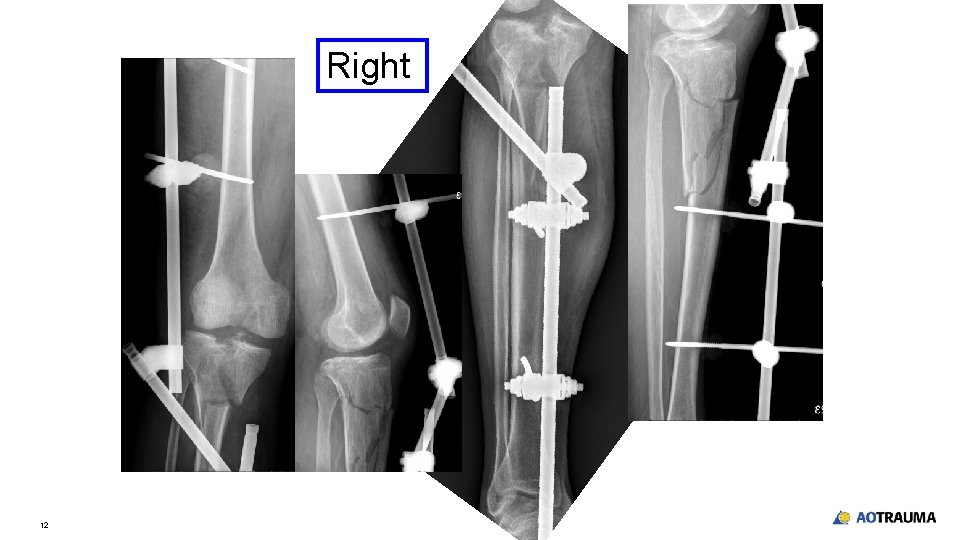

Right 12

Take-home messages • • • 14 After resuscitation in multiple-fracture patients, secondary survey is important to have complete diagnosis Screening x-rays in every suspicious area X-ray should include the joint above and below the injured area Monolateral external fixation with modular technique is an effective and fast method to stabilize the fracture of long bones especially lower extremity Simple splint for upper extremity is acceptable in acute management in damage control orthopedics

Take-home messages • • 15 Drilling and application of Schanz pins are vital to reduce pin complication Knowledge of safe zone and anatomy is crucial